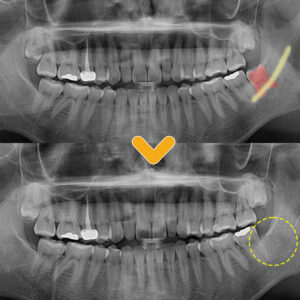

13. 야음동치과 어려운 케이스도 문제없이

야음동치과 어려운 케이스도 문제없이   안녕하세요. 모든 진료에 진심을 다하는 곳, 더플러스치과입니다. ​ 치아 중에서도 구강 내 맨 안쪽에서 맹출하는 사랑니는 영구치 중에서도 마지막에 맹출하기 때문에 제3대구치 라고도 불립니다.   일반적으로 사랑니는 17세~25세 사이에 맹출하며 첫사랑이 시작되는 시기에 나온다고 하여 사랑니라고 불리곤 하는데요, 사람마다 사랑니의 맹출 개수와 위치, 크기, 방향은 더보기…